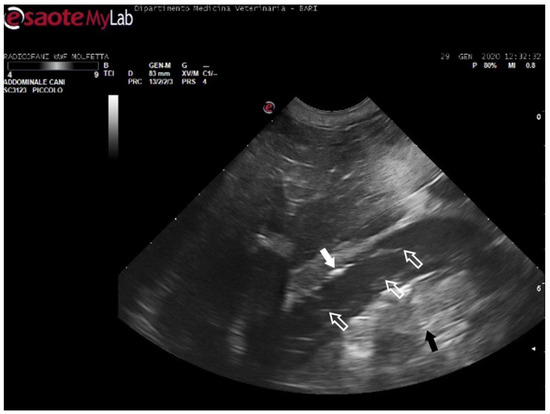

In 11 sea turtles (37, 9%), the ultrasound examination revealed the presence of emboli in various districts, often in limited quantity. Those emboli varied in size but were generally considered microemboli. They were observed to enter the bloodstream in a cascade, resulting in slower and intermittent blood flow on Color Doppler ultrasound. Ultrasonography provided distinct visualization of the liver parenchyma and its vessels, allowing for a clear view of the intestinal loops and their associated circulation. The larger emboli were consistently found adhering to the vessel walls, while smaller emboli occasionally detached and flowed into the bloodstream (Figure 5) (Video S1).

Figure 5.

Ultrasound scan from the right prefemoral window shows an aggregate of medium-sized microemboli adhered to the wall of the iliac vein (white arrow), releasing very small emboli into the bloodstream (empty white arrows). The black arrow indicates the renal parenchyma.

The patients displaying these ultrasound findings were placed in the mild category following Parga’s method [17]. In some animals within this group, ultrasonography revealed emboli in multiple areas compared to those identified on radiographs. Additionally, in a turtle that appeared radiographically negative, ultrasound exams detected the presence of microemboli in the renal arteries on both sides, as well as in the left subclavian artery (Figure 6).

Figure 6.

Ultrasound scan from the ventral cervical window revealing an aggregate of sizable microemboli (empty white arrow) in transit within the bloodstream of the left subclavian artery.